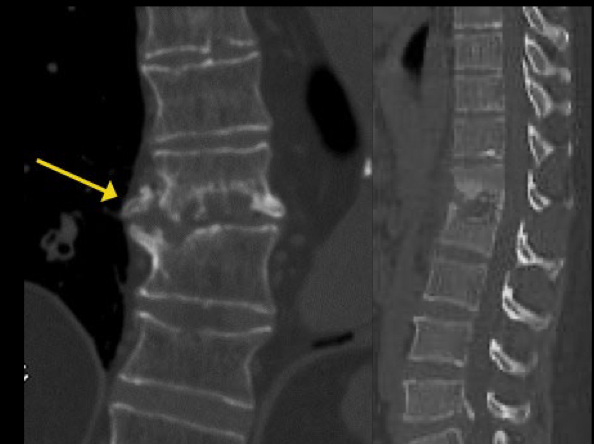

tc es muy util si o no en espondilodiscitis

A

noo

Se ve perdida de morfologia vertebral

Irregularidad plataformas